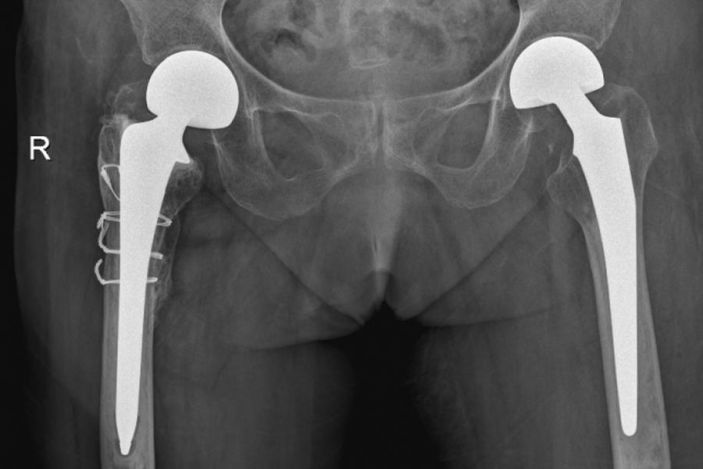

△右側(R)是賴婆婆3年前跌斷股骨術後,左側是本次手術術後。